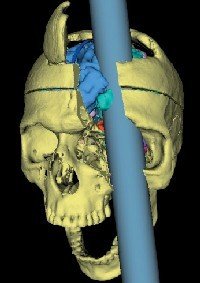

뇌와 감정의 관계와 관련된 유명한 일화의 주인공이다. 게이지는 미국의 어느 한 철도 공사 조직의 감독관이었다. 1843년 9월 13일, 25살의 게이지는 동료들과 함께 버몬트 주의 한 철도 공사에서 일하고 있었다. 구멍에 폭발물을 넣고 철 막대기로 구멍의 표면을 고르게 하기 위한 작업을 하던 중 실수로 주변 바위를 쳐 다이너마이트가 폭발하였고 그 폭발의 충격으로 철 막대기가 게이지의 왼쪽 뺨에서 오른쪽 머리 윗부분으로 뚫고 지나가버렸다. 그 결과, 그는 두개골의 상당 부분과 왼쪽 대뇌 전두엽 부분이 손상되는 심각한 상처를 입게 되었다.

게이지는 Dr. John Martyn Harlow에게 치료를 받아 다행히 죽을 고비는 넘겼지만 그의 머리에는 9cm 가 넘는 지름의 구멍이 생겨 있었다. 그가 죽을 것이라는 것은 어느 누구도 의심하지 않던 상황이었다. 그러나 사고 후, 몇 주동안 수많은 감염들이 생겨났지만 약 한 달이 지나자 그는 완벽하게 회복되었다. 그 후, 할로우 의사는 게이지의 가족과 몇 년동안 함께 지내며 게이지의 행동들을 관찰한 후 Recovery from the Passage of an Iron Bar Through the Head 라는 글을 발표했다.